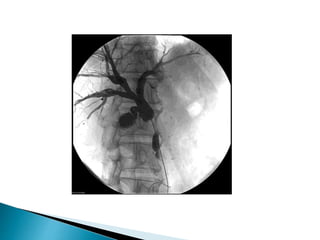

A Initial cholangiogram reveals stricture in the common hepatic duct near the previous

surgical clips.

b Balloon dilation of stricture.

c Placement of multiple stents over two procedures.

D Cholangiogram after stent removal showing stricture resolution.

Endoscopic treatment of post-cholecystectomy

biliary stricture using plastic biliary stents.